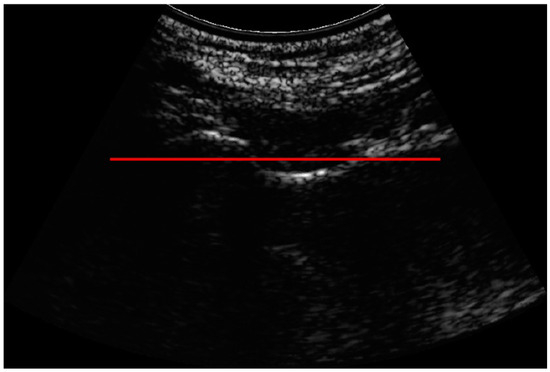

Positioning the Probe